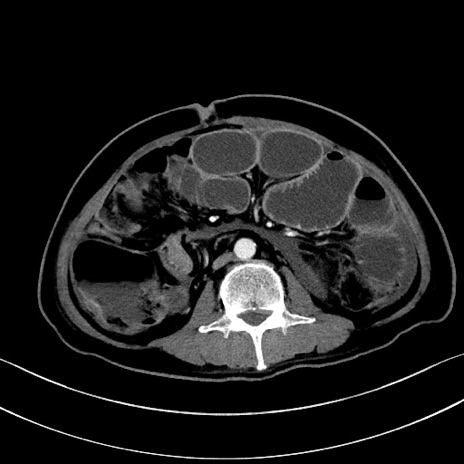

冠状断像

【症例】60歳代男性

【主訴】嘔吐

【現病歴】胃癌にて胃全摘後。食思不振が悪化し、夜中に嘔吐することがある。

【既往歴】胃癌、胃全摘、脾摘、胆摘後

【データ】WBC 5900、CRP 10.56